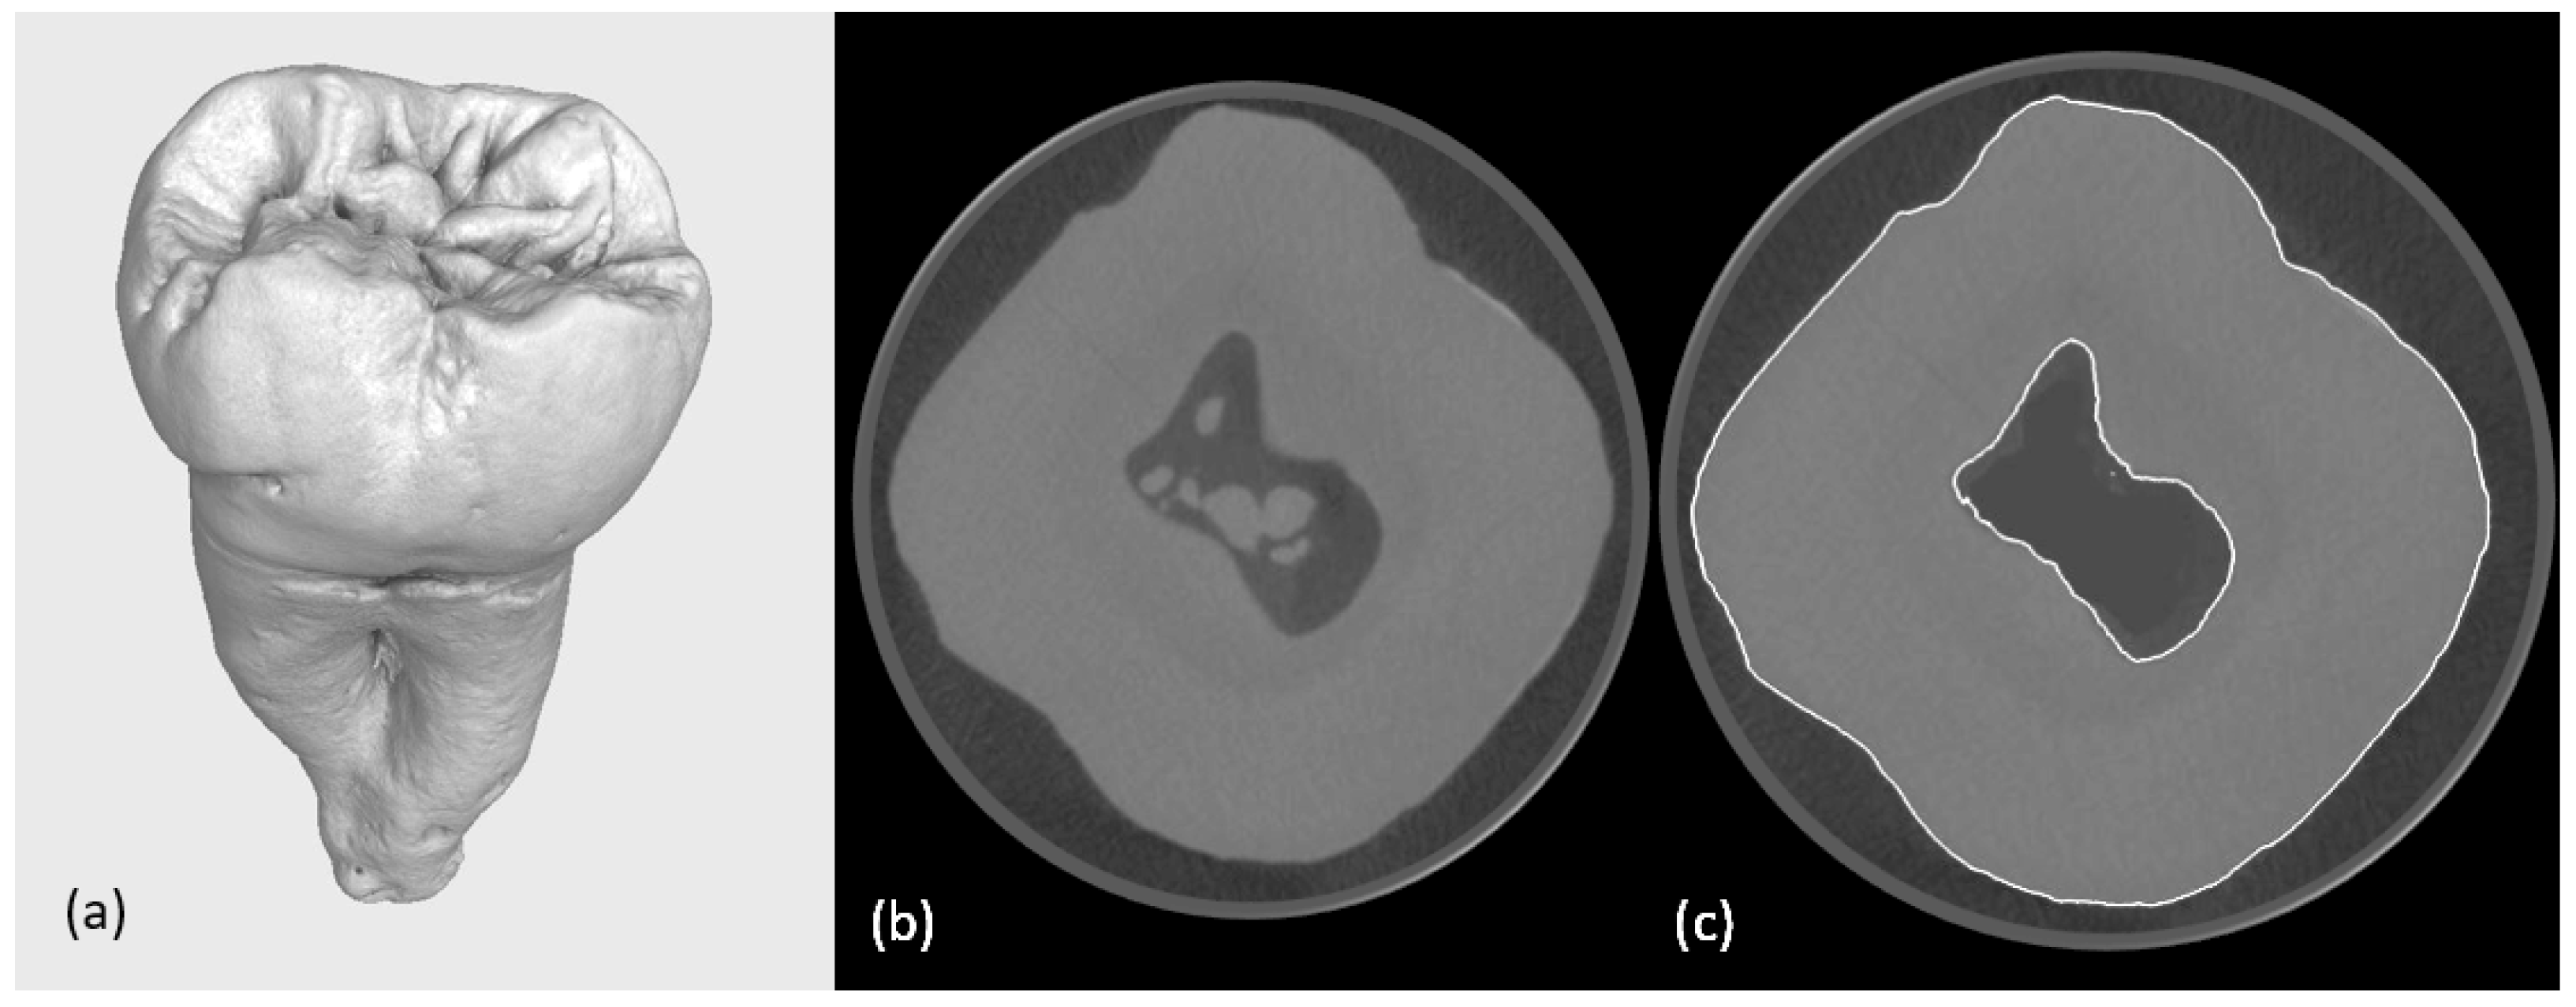

2.1. Selection of Tooth

2.2.1. First Micro-CT Scanning

2.2.4. Second Micro-CT Scanning (Post-Cavity Preparation)